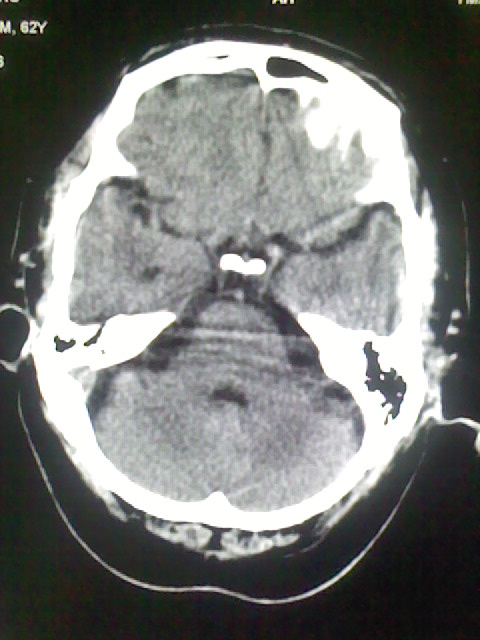

标题: CT15555:头痛 10余日 来诊大家帮忙看看

脑萎缩

脑沟、裂增宽,提法脑萎缩,建议mt检查。

脑萎缩,以小脑为著。

脑沟、裂增宽,提示脑萎缩

老年脑

支持轻度脑萎缩。